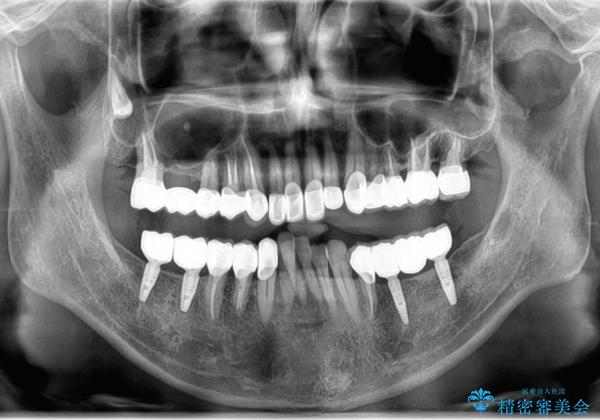

[メタルフリー] 虫歯・銀歯だらけの口腔内を全顎治療

- 銀歯だらけの見た目と、歯の磨きにくさの改善を求めて来院されました。

銀歯の下には虫歯の再発が見られたり、根尖病変や歯周病、噛み合わせといった複合的な問題が認められます。

残すことのできる歯には根管治療・歯周病治療を行い、やむを得ず抜去の必要な部位はブリッジやインプラントを用い、安定した噛み合わせ・歯の磨きやすい環境を確立していきます。